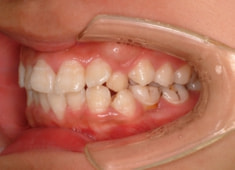

治療前

治療開始時